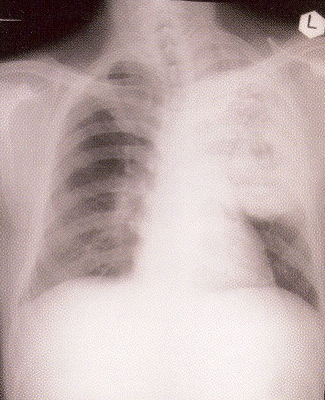

The patient was a 36-year-old man with a smoking history of 15 pack-years. He was a non- drinker and worked as a van driver delivering chicken. He enjoyed good past health and gave no recent traveling history. He first became unwell in Jan 2001 when he noted increasing lethargy, headache, jaw numbness and dry cough. He saw various GPs without improvement and was eventually admitted into a HA hospital on 13/1/2001 with worsening jaw pain and a cough which was now productive of bloodstained sputum. He had a low-grade fever on admission. His admission CXR showed a huge left upper lobe mass and right upper lobe nodules (Fig 1). A CT thorax confirmed a necrotic lung mass with mediastinal lymphadenopathies (Fig 2). Bronchoscopy was performed via the oral route due to nasal congestion and there was complete occlusion of his left upper lobe orifice with nodular mucosa in the right upper and middle lobes. The endoscopic diagnosis was carcinoma of the lung but both the histology of the bronchoscopic biopsy and a subsequent fine needle aspiration of the lung lesion yielded necrotic material only. He was treated with antibiotics and analgesics for presumed chest infection but his condition deteriorated with increasing respiratory distress.